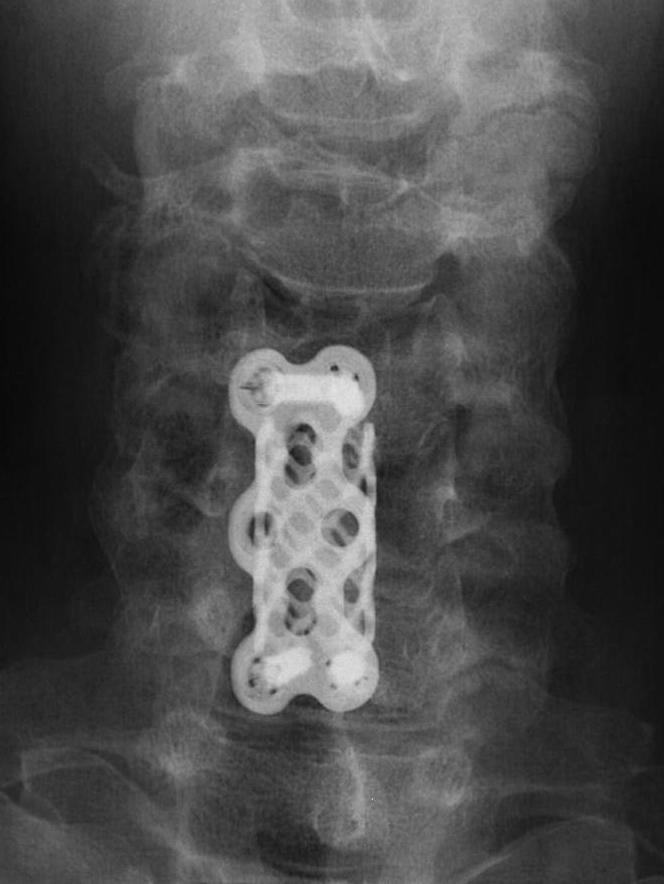

Corpectomy

Concept

Can remove body with disc above and below and decompress multiple levels

Indication

- multilevel disease

- soft and hard disc causing compression

- kyphotic deformity

Complications

Risk of graft extrusion / hardware failure - fewer points of fixation